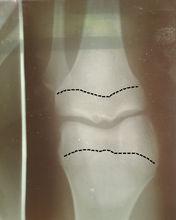

長骨的兩端膨大,稱為骺。幼年時,骨幹與骺之間有透明軟骨,成年後軟骨骨化,骨幹與骺融為一體,其間遺留的痕跡,叫骺線。

骨垢線長骨的兩端膨大,稱為骺.幼年時,骨幹與骺之間有透明軟骨,成年後軟骨骨化,骨幹與骺融為一體,其間遺留的痕跡,叫骺線.